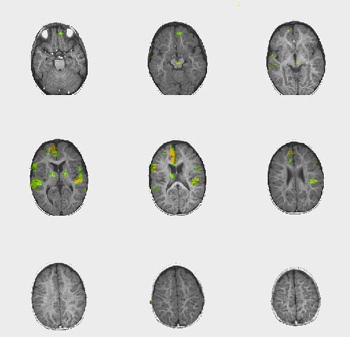

| Caso 2 |

Niño de 18 meses de edad con parálisis cerebral leve. |

ACTIVADO: Presentación de la voz de la madre, pregrabada, en la que usa palabras y sonidos familiares

DESACTIVADO: Nada. Paciente sedado con propofol |

0,0005 |

3,2 |

| Activación |

La activación de las áreas auditivas está bien definida. Se observa activación bitalámica. No se comprende claramente la fuerte activación del lóbulo frontal parasagital derecho. |